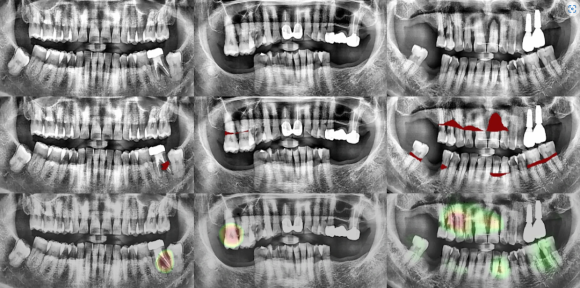

다양한 파노라믹 진단 과정

해당 기술은 충치균과 세균의 활성을 수치화 하여

정확한 충치 진단과 크랙 진단에 객관적이고 정확한 자료를 제공해 줍니다.

Q-ray를 이용한 충치 감별

Q-ray를 이용한 Crack 감별

Q-ray를 이용한 충치감별